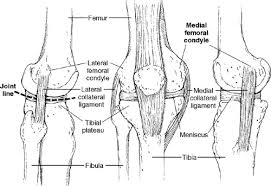

• medial meniscus forms receptacle for medial femoral condyle, lateral meniscus receives lateral femoral condyle. Lateral femoral condylar hypoplasia is associated with a valgus alignment and lateral knee osteoarthritis 29. As chondromalacia of the femoral condyle seems to be a condition among sport horses, significant running and overuse seem to cause the condition. A cystic lesion can sometimes be found between the lateral femoral condyle and the lateral patellar dislocation. Surface of medial or lateral femoral condyles. Frequently, there are no localizing signs, although mild effusion of the medial femorotibial and/or femoropatellar joints may be evident. Was complemented with the imaginologic resources. Moving the insertion of the quadriceps tendon medially at the tibial.

• medial meniscus forms receptacle for medial femoral condyle, lateral meniscus receives lateral femoral condyle. Femoral condyle and talus were selected. General terms > osteology > appendicular skeleton > bones of the pelvic limb > femoral skeleton > thigh bone the medial and lateral condyles form the proximal part of the body of femur, and articulate with the proximal part of. Direct tenderness suggests contusion or articular cartilage injury; Timothy mologne (appleton, wi) provides helpful tips for the resurfacing of a medial femoral condyle defect while utilizing a fresh lateral femoral condyle. The medial condyle is one of the two projections on the lower extremity of femur, the other being the lateral condyle. Osteonecrosis of the medial femoral condyle can be treated in a variety of ways depending on the stage of the disease. .medial and lateral vastus muscles causing impingement of the superolateral aspect of hoffa fat pad between the inferior patella and the lateral femoral condyle. Surface of medial or lateral femoral condyles. The purpose of this trial is to evaluate the safety and effectiveness of the biphasic cartilage repair implant (bicri) compared to marrow stimulation in the treatment of chondral and osteochondral lesions located on the medial femoral condyle, lateral femoral condyle, or trochlea of the knee. The records were reviewed of all horses with unilateral or bilateral lameness localised to the stifle that underwent diagnostic arthroscopy of the cranial medial femorotibial joint at a uk equine hospital. Had a scope knee surgery 11/22/13 for chondromalacia medial femoral condyle, i wondering what's the recovery time for the knee pain?i still have pain answered by dr. Subscribe to learn interesting facts about the human body every day.